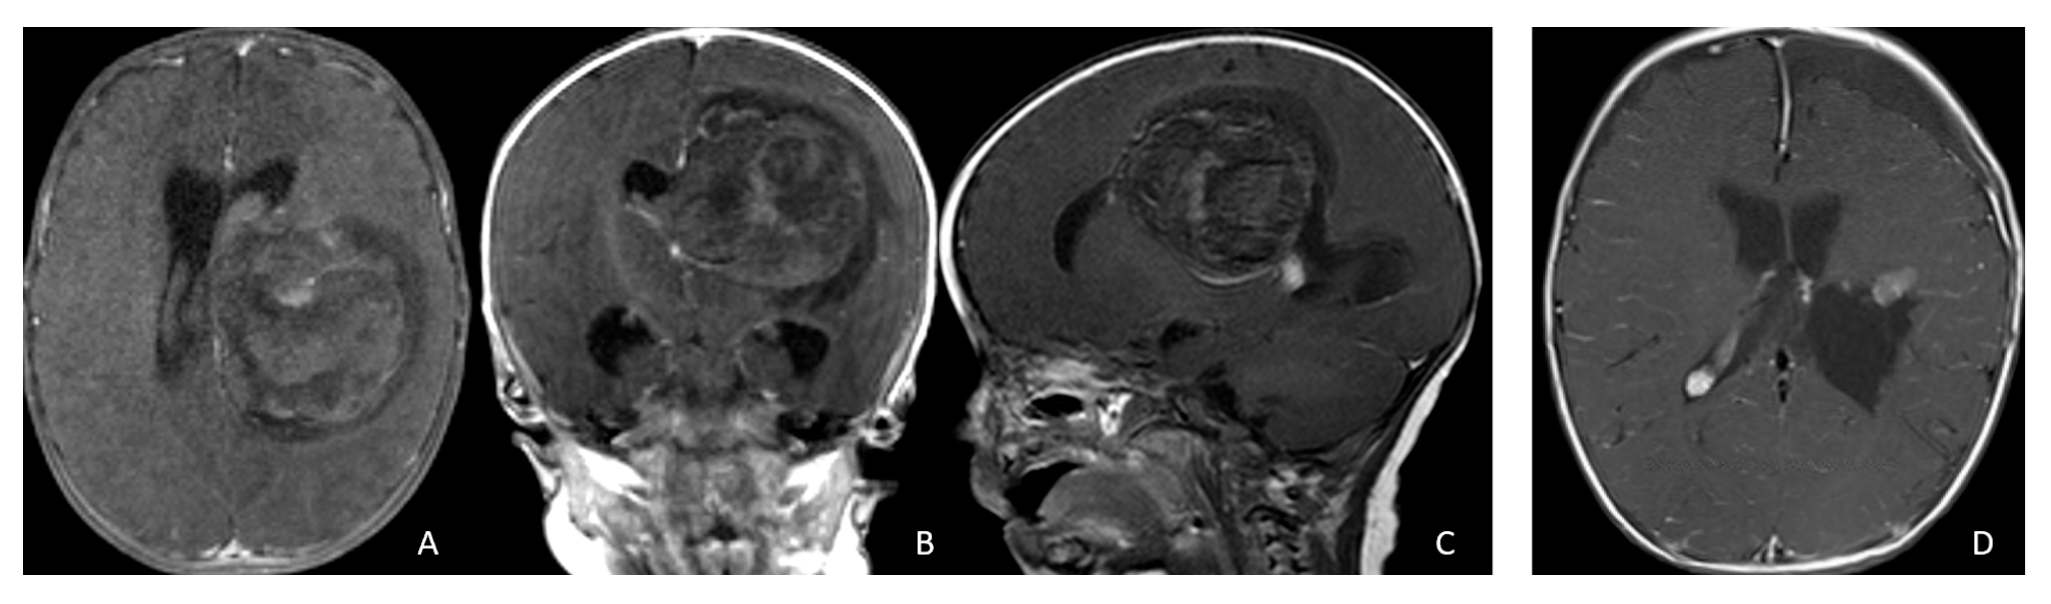

Tumor epicenters and patterns of extension were best delineated by operative observations combined with preoperative and postoperative imaging (Figure 1). Three patients had tumors involving both the temporal and frontal lobes that crossed the Sylvian fissure (Figure 2). Despite appearance of thalamic involvement on preoperative imaging, two patients had tumors primarily occurred in the basal ganglia, which became more evident on postoperative MRI (Figure 3). Additional hemispheric tumor extended into the thalamus. These lesions were resected via a trans-sylvian approach.

Figure 1.

Cerebral lobar ATRT. (A–D): 20-month-old boy with a parietal intraparenchymal ATRT. Preoperative axial images (A,B) and postoperative axial (C) and coronal (D) images confirm the intraparenchymal location following resection. (E–H): 26-month-old boy with a large heterogeneous frontal mass with multiple peritumoral cysts. Preoperative axial (E) and coronal (F) images, and postoperative axial (G) and coronal (H) images after gross-total resection support a frontal lobe origin despite of the basal ganglia origine as the preoperative imaging suggetsed.

Figure 3.

Basal ganglia ATRT. (A–D): Post contrast MR images ((A)-axial, (B)-coronal) of 13-month-old boy with deep seated ATRT. Note the solid tumor with peritumoral cysts at the basal ganglia with one cyst extending to the thalamus. Post-resection MR images ((C)-axial, ((D)-coronal) show the tumor resected cavity in the basal ganglia with the thalamus clear of tumor involvement. (E–H): Post contrast MR images ((E)-axial, (F)-coronal) of a 23-month-old boy with a large ATRT of deep temporal lobe and the insula extending to the basal ganglia. The tumor was predominantly in the basal ganglia as shown postoperative MR ((G)-axial, (H)-coronal).

Three tumors were predominantly located within the ventricle, two within the lateral ventricle and another within the third ventricle (Figure 4). None appeared to arise from the choroid plexus or as pedunculated lesions from the ependymal layer; rather, operative and imaging features supported a paraventricular origin because of diffuse attachment to the ventricular wall. Two large hemorrhagic hemispheric tumors extended into the lateral ventricle. These paraventricular ATRT extends into the lateral ventricle (Figure 5).

Figure 4.

Intraventricular ATRT. (A–D): A 7-month-old boy with ATRT within the left lateral ventricle with associated hydrocephalus shown on MR images ((A), axial; (B), coronal; (C), sagittal). Note irregular peritumoral cysts and ependymal invasion which was confirmed at surgery. Postoperative MR image ((D), axial) shows a gross-total resection. The patient had a history of rhabdoid tumor predisposition syndrome. (E–H): A 34-month-old boy with MR images ((E), axial; (F), coronal; (G), sagittal) showing an intraventricular mass at the anterior horn based on the septum pellucidum. ATRT was originated at the junction of the septum pellucidum. Post-contrast MR ((H), axial) confirms resection. (I–L): Post-contrast MR images ((I), axial; (J), coronal; (K), sagittal) of a 3.5-year-old boy demonstrate a large, enhancing third ventricular ATRT with partial extension into the lateral ventricle. The lesion was removed via an interhemispheric transcallosal approach ((L), sagittal).

Figure 5.

Paraventricular ATRT with ventricular extension. (A–D): A 3-month-old girl who presented with emesis followed by acute decerebrate posturing. Post-contrast MR images ((A), axial; (B), coronal; (C), sagittal) reveal a large hemorrhagic mass in a deep centrencephalic location. Postoperative MR ((D), axial) shows a focal dilation of the lateral ventricle after subtotal resection of a parietal para-ventricular ATRT.

Three patients presented with massive subdural/parenchymal masses involving both cerebral hemispheres across the falx cerebri; two bi-frontal and one in bi-occipital (Figure 6). These tumors appeared to originate within the cerebral hemispheres and permeate or traverse the falx cerebri, resulting in bilateral disease.

Figure 6.

Bi-hemispheric ATRT. (A–E): MR images ((A), axial; (B), coronal; (C), sagittal) of a 4-year-old boy show a bifrontal ATRT crossing the falx cerebri, with heterogeneous enhancement. The corpus callosum is compressed posteriorly. At surgery, left frontal component invades and permeates through the falx with extension into the right subdural space. Postoperative images after bifrontal craniotomy ((D), axial; (E), coronal) show tumor resection. Bi-occipital hemispheric ATRT. (F–J): MR images ((F,G), axial; (H), coronal) of a reveal a 22-month-old girl large, inhomogeneous left occipital lobe mass crossing the midline into the right occipital lobe. The lesion invades the posterior falx cerebri and extends into the medial occipital lobe of the right side. A highly vascular tumor was resected via a left occipital craniotomy; the right occipital component was not removed with concern of blindness due to preexisting right homonymous hemianopia. She received chemoradiation with durable disease resolution for over 15 years, as shown on follow-up post-contrast MR ((I), axial; (J), coronal).